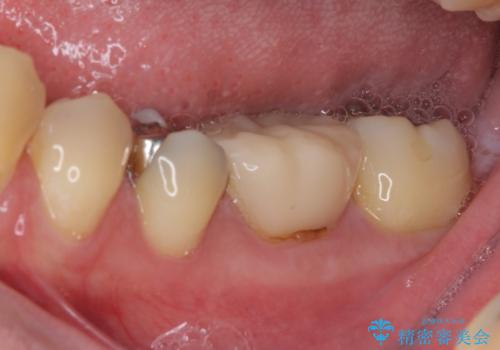

- 保険診療で装着した奥歯の白いクラウンの具合がよくないとのことで来院された患者様です。

保険診療で安価に白いクラウンが入れられるということで選択されたそうですが、装着後に痛みを感じたり、ものが挟まって不快であったりと不便が多いため、セラミッククラウンにて補綴治療を行うこととしました。

保険診療では、安価に白いクラウンを装着できる代償として、歯とクラウンの境目が不適合であったり、歯と歯の間にものが挟まりやすかったりと、不快な思いをされることがしばしばあります。